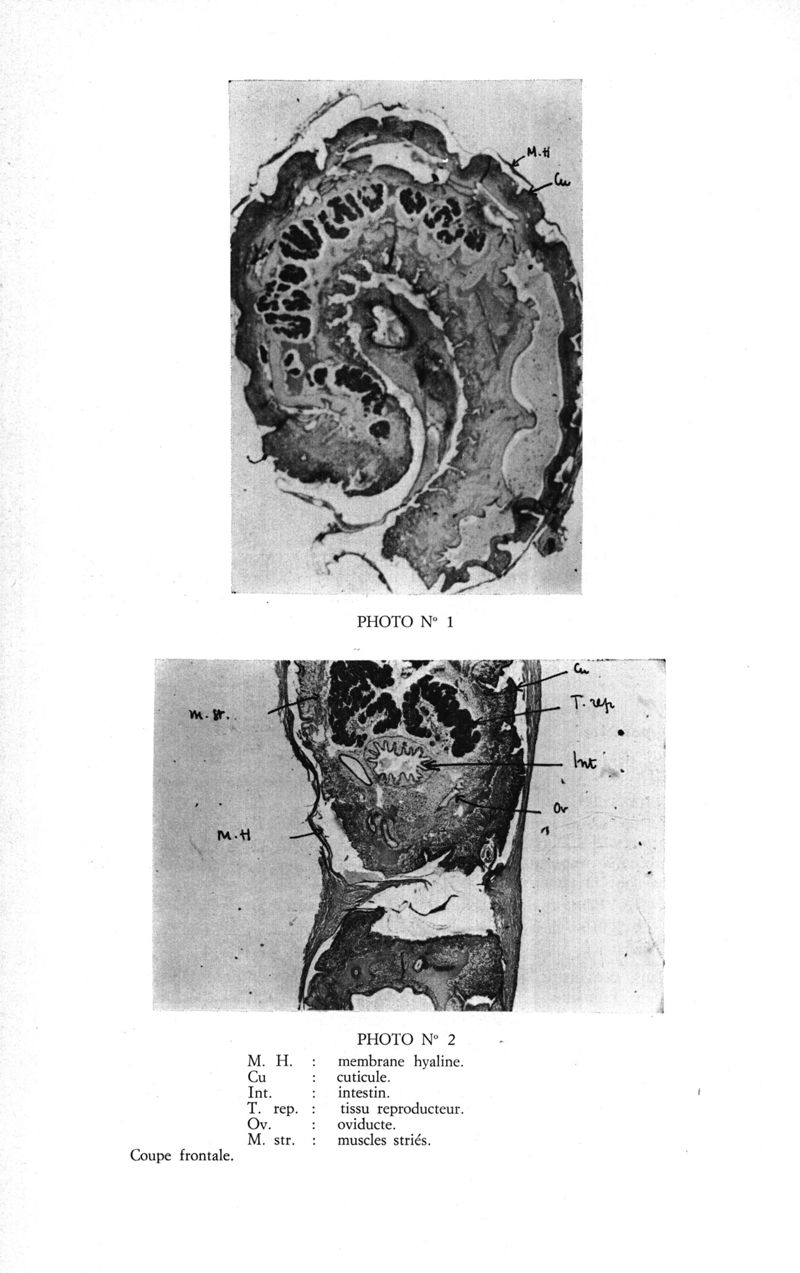

Médecine tropicale: revue française de pathologie et de santé publique tropicales

. - Marseille, 1974.